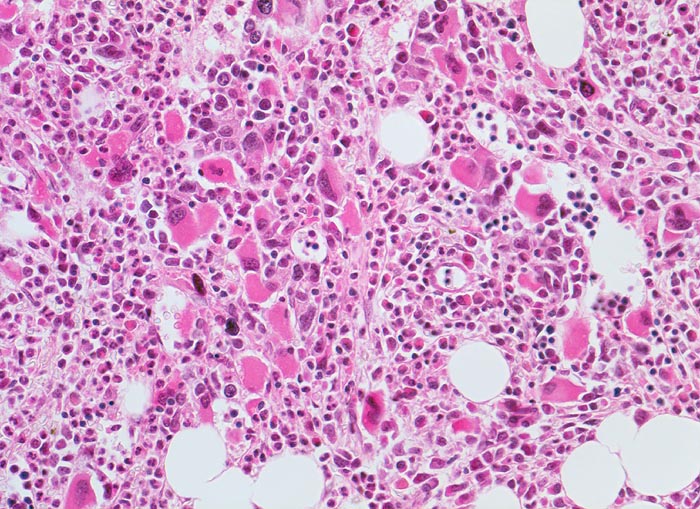

Morphologie

Morphologische Merkmale:

• Osteosklerose: verplumpte und breite Knochenbälkchen.

• Kollagenfibrose.

• Dilatierte Sinusoide mit intrasinusoidaler Blutbildung.

• Vermehrung von atypischen, in Gruppen liegenden Megakaryozyten mit abnorm lobulierten Kernen.

• Nacktkernige (zytoplasmaarme) und vergrösserte Megakaryozyten.

• Hyperplastische ausreifende Myelopoese.

• Hypoplastische Erythropoese.

• Retikulinfaserfibrose des Marks vorhanden aber in der HE Färbung schwierig quantifizierbar.